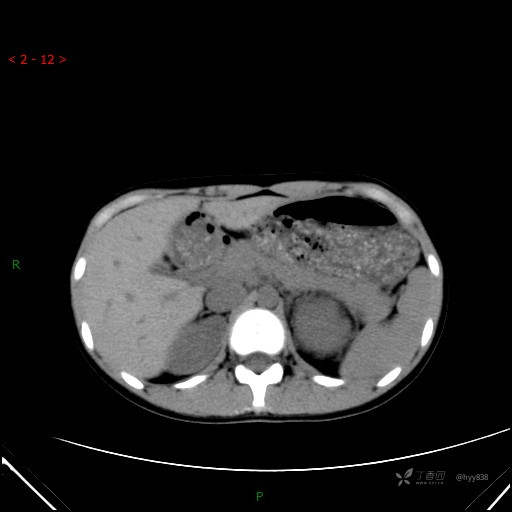

腹部CT平扫